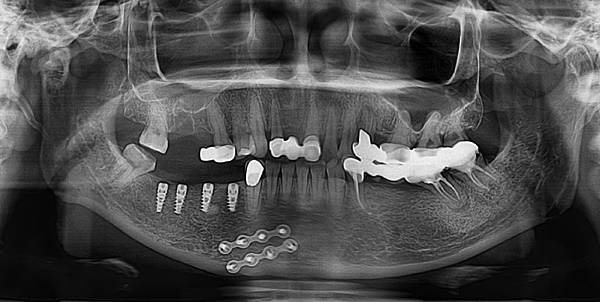

這是我植牙進行後,植入植體後的X光片,醫師植入植體後,在看診時間也拿出來跟我詳細解釋一番。

↑右側下顎植入人工植體的X光圖(先植入右下顎的植體)